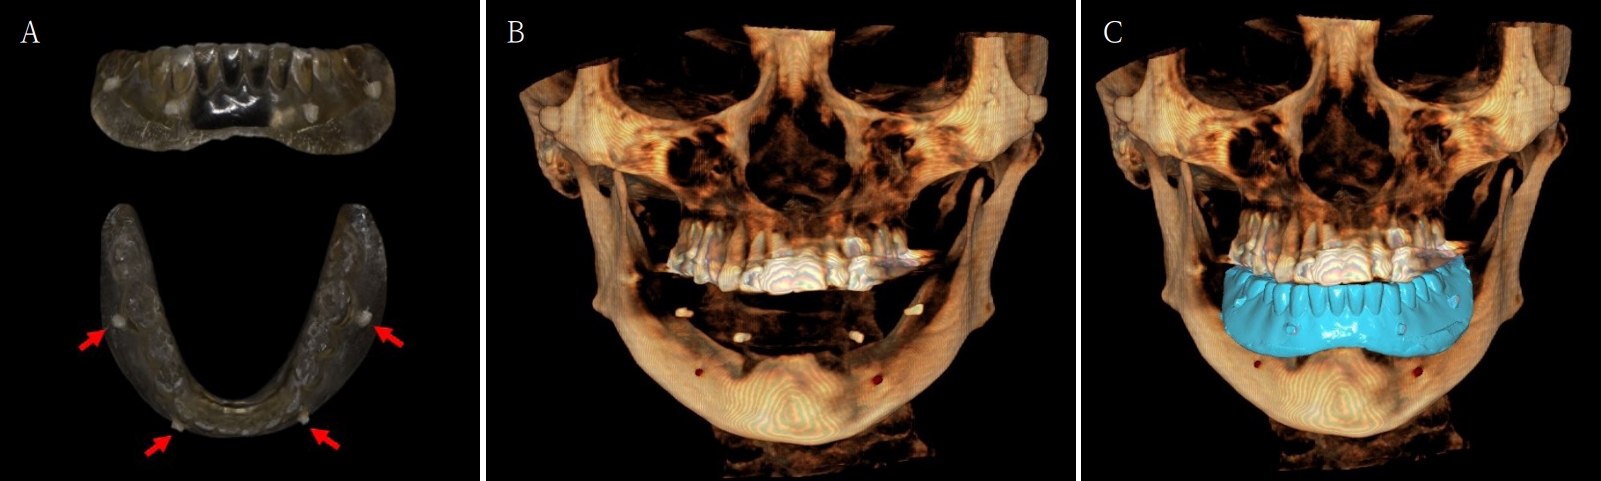

Fig. 6.

A. 3-dimensional (3D) printing denture is marked with radio-opaque resin marker. B. CBCT is taken with the 3D printing denture with marker. C. Superimposition of CBCT and model scan data is completed.

jkda-2025-63-7-001f6.jpg

환자가 적응한 임시 의치를 모델 스캔(Medit T710, Medit, Seoul, Korea)하여 프린팅용 레진(Graphy Tera Harz SG-100, Graphy, Seoul, Korea)을 이용하여 3D 프린팅하였고, 출력된 의치에 방사선 불투과성 레진(G-æenial Universal Flo, GC, Luzern, Swiss)을 부착하여 레진 마커를 형성하였다. 레진 마커를 부착한 프린팅 의치를 장착한 채로 콘빔 전산화 단층촬영(CBCT, R2 Studio Q, Megagen, Seoul, Korea)를 촬영하였다(Fig. 6). 촬영한 CBCT 데이터와 의치 스캔 파일을 중첩하여 CAD 소프트웨어(R2 Studio Q, Megagen, Seoul)를 통해 이상적인 임플란트 식립을 계획하였다. 전후방 거리를 연장하여 적절한 캔틸레버를 부여하기 위해 전방부에 3개의 임플란트를 식립하고, 양측 후방부에는 약 30도 경사진 임플란트를 식립하도록 계획하였다(Fig. 7).